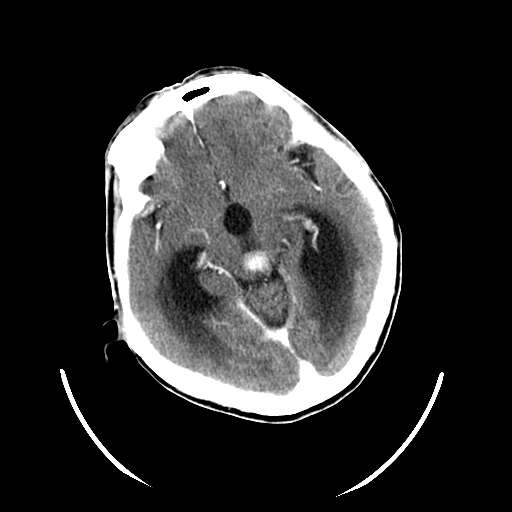

以下是引用zhangzhongshou在2007-10-8 19:16:00的发言:[br]大脑大静脉瘤[br]

以下是引用hhcckk在2007-10-9 10:03:00的发言:[br]galen';s静脉瘤又称大脑大静脉瘤,是由于动静脉短路,大量血流进入galen';s静脉(大脑大静脉),造成该静脉瘤样扩张所致,病理上典型的galen';s静脉瘤包括一明显扩张的囊状galen';s静脉和引流galen';s静脉的短路血管,,这些短路血管多来源于颈内动脉系统或基底动脉系统,多异常扩大、迂曲。巨大的galen';s静脉瘤可造成中脑压迫,导水管闭塞,引起梗阻性脑积水。[br]galen';s静脉瘤ct表现较典型,根据其部位、形态、增强前后表现及脑积水表现较易诊断。[br]支持张主任,此病人病灶强化明显,正常松果体增强后在病灶的后方可见,可以再做个mr,血管性的病灶在mr上有流空效应,增强后明显强化,诊断更有把握